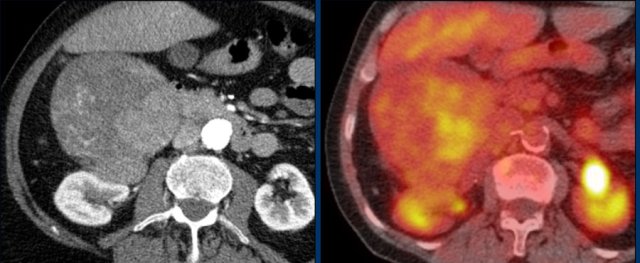

This axial venous CT shows a very bulky right adrenal mass, suspicious for a malignancy, based on the large size and heterogeneity.

This lesion is an adrenocortical carcinoma, but in contrast to the former example, subsequent FDG PET-CT performed for staging purposes showed only mild uptake and only in the most avidly enhancing part of the tumor.

Most adrenocortical carcinomas show intense FDG-uptake.

This lack of FDG-avidity might be due to a lower grade tumor with lower mitotic rate or large hemorrhagic or necrotic components.

First postoperative axial venous phase CT performed 3 months after left adrenalectomy for a large adrenocortical carcinoma showing an enhancing nodule posterior to the left kidney.

Restaging FDG PET-CT showed intense uptake in only this lesion, which proved to be a metastasis on subsequent follow-up imaging.

The left renal subcapsular hematoma is unrelated.